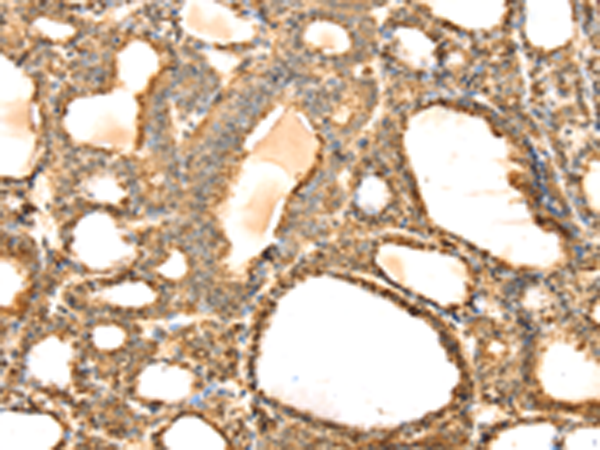

分类: 科研抗体货号: P08749别名: SeP; SELP; SEPP; SEPP1应用: WB,IHC反应种属: Human